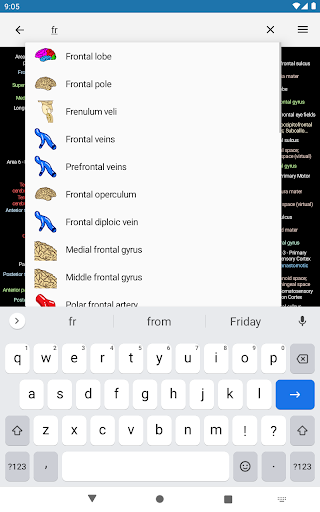

*Improving performance of anatomical structure search

*Find your anatomical parts more easily thanks to the new, more intuitive and powerful search feature

-Implementation of search by patronyms.